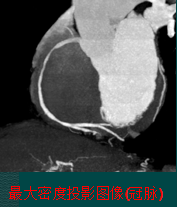

心脏组织自动分割

心脏组织自动分割包括:左心房、左心室、右心房、右心室、升主动脉和左右冠状动脉的分割。

![]()

心脏VR视图可直观展示各支冠脉血管与心脏的对应关系。其劣势是无法显示血管腔内病变,且有些冠状动脉无法得到最佳显示角度。

![]()

冠状动脉的VR视图只显示部分升主动脉和冠状动脉血管,可转动图像至最佳角度显示需要观察的冠状动脉。

血管树解析

血管树的解析过程是冠脉中心线的自动提取和分析的过程。

![]()

在心血管的狭窄分析与检测、虚拟内窥镜自动导航漫游、冠状动脉多平面重建的视图显示、血管曲面重建等图像几何形态分析及相关领域中,管状器官的中心线具有非常广泛的应用。